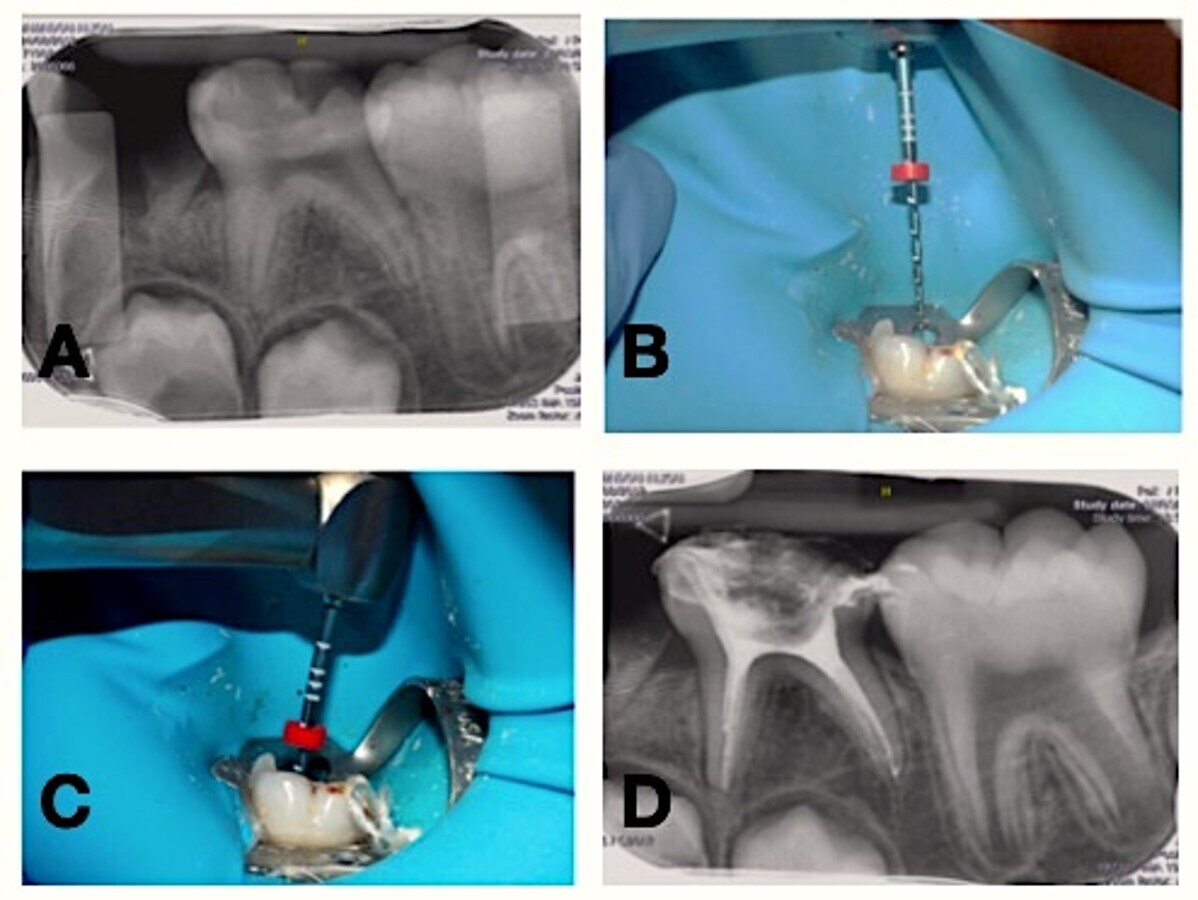

Figura 2. Procedimiento con técnica reciprocante. A: radiografía periapical inicial. B y C: imagen clínica de la instrumentación con lima Reciproc blue R25. D: radiografía periapical final.

En el paciente B, se eliminó el tejido pulpar radicular con el sistema reciprocante: lima R25 de Reciproc® blue (Figura 2) de 21mm de longitud, conicidad de .08 y sección transversal en forma de “S”. Para la instrumentación se utilizó el motor Gold Reciproc® (VDW, Germany) con el modo “reciproc all” y se realizaron movimientos de picoteo, desplazando el instrumento lentamente y con una presión muy ligera. Después de realizar 3 picoteos se retiró el instrumento del conducto.

Todos los conductos fueron irrigados con hipoclorito de sodio al 2.5%; en cada diente se irrigaron 5ml de NaOCl empleando una jeringa con aguja de salida lateral. Posteriormente, los conductos fueron secados con puntas de papel del calibre de la última lima utilizada. Se realizó la obturación de los conductos con pasta yodofórmica e hidróxido de calcio (Vitapex®; Neo Dental International Inc., USA), mediante su punta aplicadora, compactando posteriormente con una bolita de algodón. La cámara pulpar se recubrió con una pasta provisional de óxido de zinc Eugenol (IRM®; Dentsply Caulk, USA), y se realizó una radiografía final con paralelizador. En ambos casos se colocó una corona de acero inoxidable 3M (3M ESPE, USA) cementada con cemento de ionómero de vidreo (Ktac-Cem®; 3M ESPE, USA).